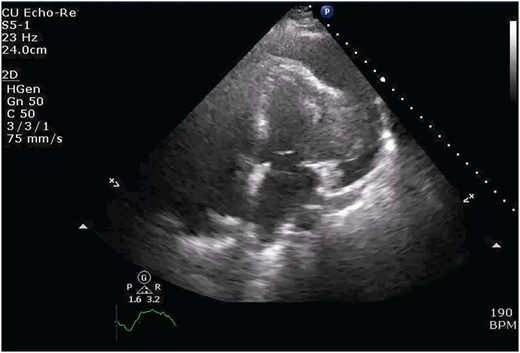

Chest X-ray found an enlarged cardiomediastinal silhouette with mild pulmonary edema (Fig. 1). A computed tomography angiography (CTA) of the chest to rule out pulmonary embolism (PE) was ordered. After the patient returned from imaging, she was found to have a heart rate of 178. Patient was awake, did not appear to be in any more distress and remained hemodynamically stable. Repeated ECG showed monomorphic ventricular tachycardia, with the patient remaining non-distressed. Patient was started on i.v. amiodarone, and urgent cardiology consult was obtained. A transthoracic echocardiogram depicted a large mass measuring 5 cm by 7 cm occupying the basal and mid portion of the anterior and lateral walls of the left ventricles with large pericardial effusion located at the lateral posterior wall of the heart, findings suggestive of impending tamponade (Fig. 2). CTA of the chest reported no acute PE with a large mass (10.5 × 7.5 × 9.5 cm3) occupying the anterior wall of the left ventricle and extending to the pulmonary outflow tract (Fig. 3).

Transthoracic echocardiogram depicting large effusion within pericardial membrane with left ventricular mass.